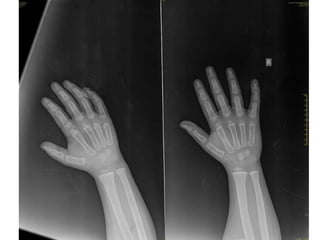

24

BONE

(hand)

OSSIFICATION

CENTRE

APPEARANC

E

CONJOINT

EPIPHYSIS

FUSION/U

NION

First Metacarpal 2-3 - 15-17

Proximal phalanges 1.5-2 - 15-18

Metacarpals 2-3 -

15-19

Middle phalanges 2-4 - 15-18

Distal phalanges 2-4 - 15-18